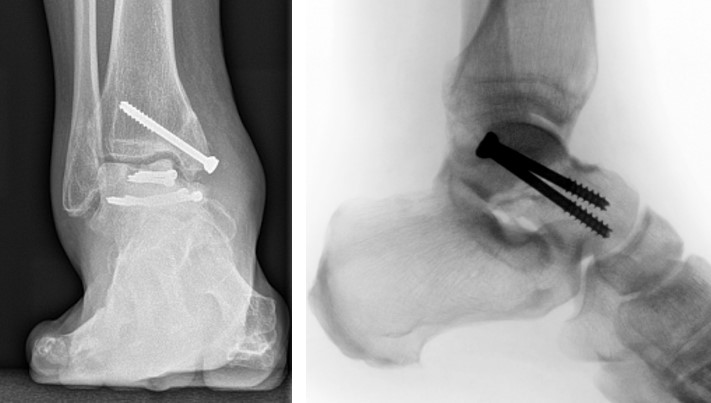

Методи фіксації: Сучасні методики включають остеосинтез гвинтами (канюльованими або кортикальними), пластинами або їх комбінацією. Анатомічна репозиція суглобових поверхонь є критичною для профілактики посттравматичного артрозу. Фіксація має забезпечувати достатню стабільність при мінімальному порушенні васкуляризації.

Артроскопічний контроль: Сучасні протоколи рекомендують артроскопічну асистенцію для верифікації якості репозиції суглобових поверхонь та видалення інтраартикулярних фрагментів.